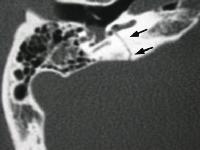

骨折類型及臨床表現通常以骨折線與岩部長軸的關係,將顳骨骨折分為3種類型:

顳骨骨折2、橫行骨折較少見。約占20%,多由頭顱壓縮性損傷引起。骨折線常起自顱後窩的枕骨大孔,橫過岩錐到顱中窩,有的經過舌下神經孔及岩部的管孔(如頸靜脈孔)、個別的可經內耳道和迷路到破裂孔或棘孔附近,因而骨折線可通過內耳道或骨迷路,還可將鼓室內壁,前庭窗、蝸窗著列,故常有耳蝸、前庭及面神經受孫症狀。如乾音性聾、眩暈、自性眼震、面癱其血鼓室等,面癱的發生率約占50%,且不易恢復。

顳骨骨折(二)橫行骨折:主要由於枕部受到暴力所致。骨折線與岩骨長軸垂直,由顱底後窩橫過岩錐到顱中窩,多從枕骨大孔或頸靜脈窩,橫過內耳道和迷路到顱中窩的破裂孔或棘孔區。內耳損傷重,耳蝸及半規管內常有出血,迷路受損時有較重的眩暈、噁心、嘔吐,檢查可有傾倒及自發性眼球震顫,可持續數周,待對側代償後症狀消失。前庭功能檢查,患側功能喪失,聽力呈感音性耳聾。傷及中耳者較少,偶有迷路損傷同時中耳內壁也被震裂,導致蝸窗膜破裂,鼓室積血,約有半數並發麵癱,且為永久性癱瘓。